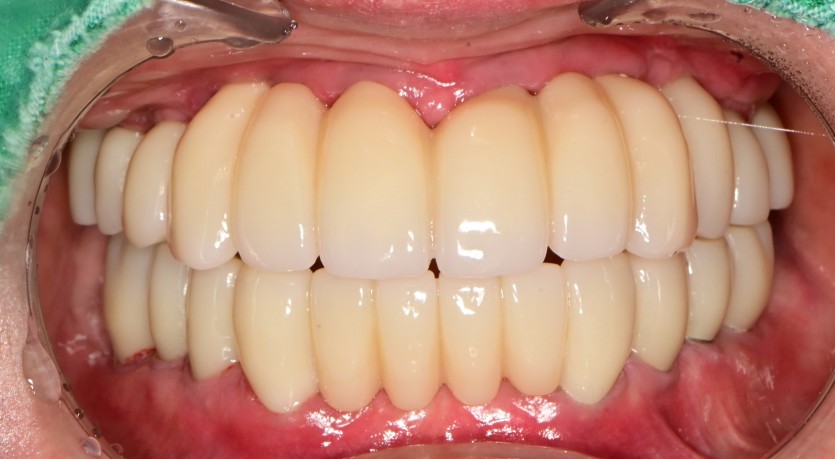

전체 임플란트 증례입니다.

18개의 임플란트로 완성하였습니다.